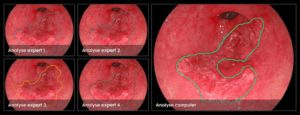

TU/e software paves the way for 100% detection of esophageal cancer